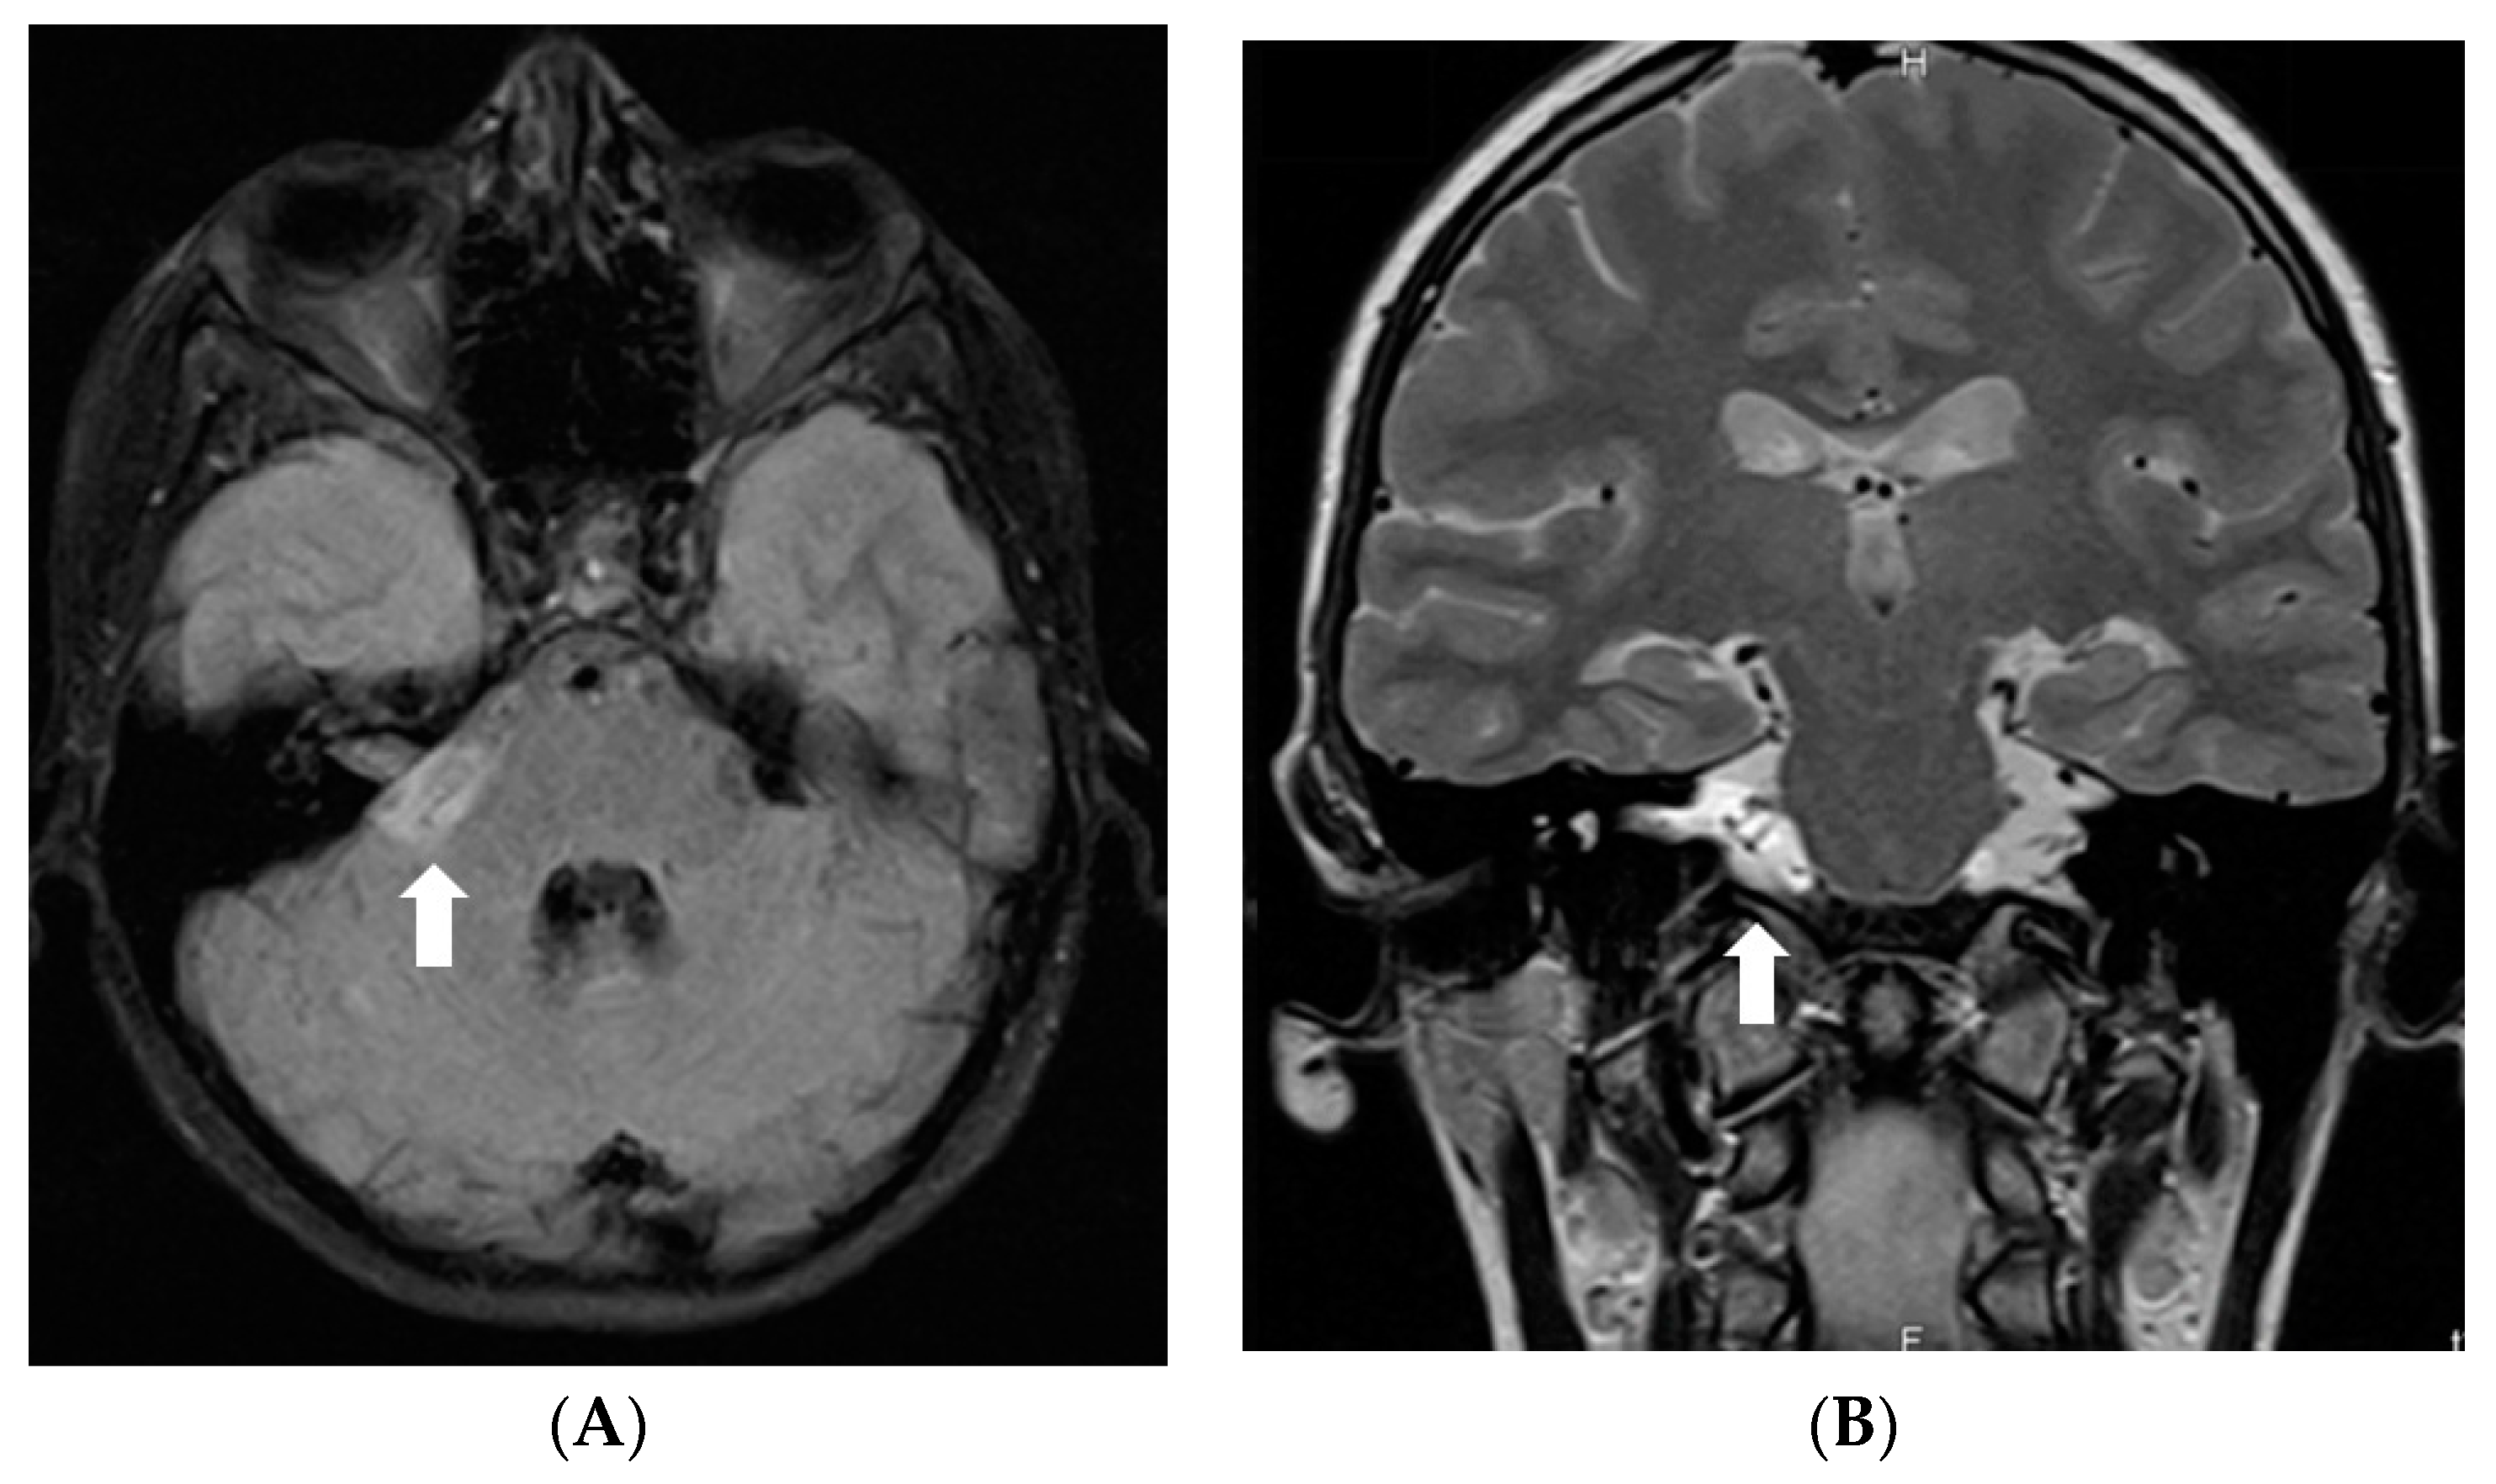

Due to impaired vision, further loss of hearing, and ability to walk, an MRI of the brain and spine was repeated in 2020. MR brain revealed residual changes—cystic leptomeningeal-subpial nodular lesions that were hypointense on T2W/FLAIR, and did not show contrast enhancement in the posterior fossa and along the basal cisterns, surrounding the brainstem, cranial nerves, and cerebellum. Imaging of spinal cord revealed cystic nodular lesions resembling those found in the brain and causing persistent, multisegmental spinal cord compression (Figure 6).

Figure 6.

Follow-up MRI of the brain and spinal cord 9 years after the onset of symptoms (November 2020): (A) Axial T2W/FLAIR, (B,C) and (D) sagittal T1W post-contrast images demonstrate residual non-enhancing cystic lesions in basal cisterns and posterior fossa surrounding brainstem and cerebellum. (D) Sagittal T1W post-contrast image shows diffuse atrophy of the cerebellum. (E,G,I) Sagittal T2W and (F,H,J) T1W post-contrast images of (E,F) cervical, (G,H) thoracic, and (I,J) lumbar spinal cord reveal diffuse intradural extramedullary mixed cystic and solid lesions that show medium contrast enhancement and slight compression of spinal cord at various levels.